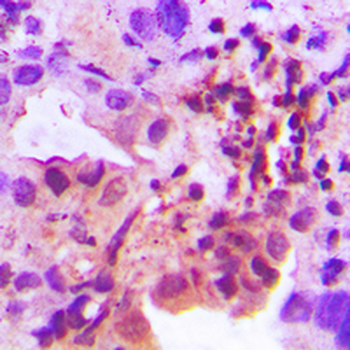

50 μl, 100 μl, 200 μl - Glucocorticoid Receptor Antibody [orb2649482]

IF, IHC, IP, WB

Human, Mouse, Rat, Virus

Rabbit

Polyclonal

Unconjugated

50 μl - Adenylate Kinase 1 Antibody [orb2649532]